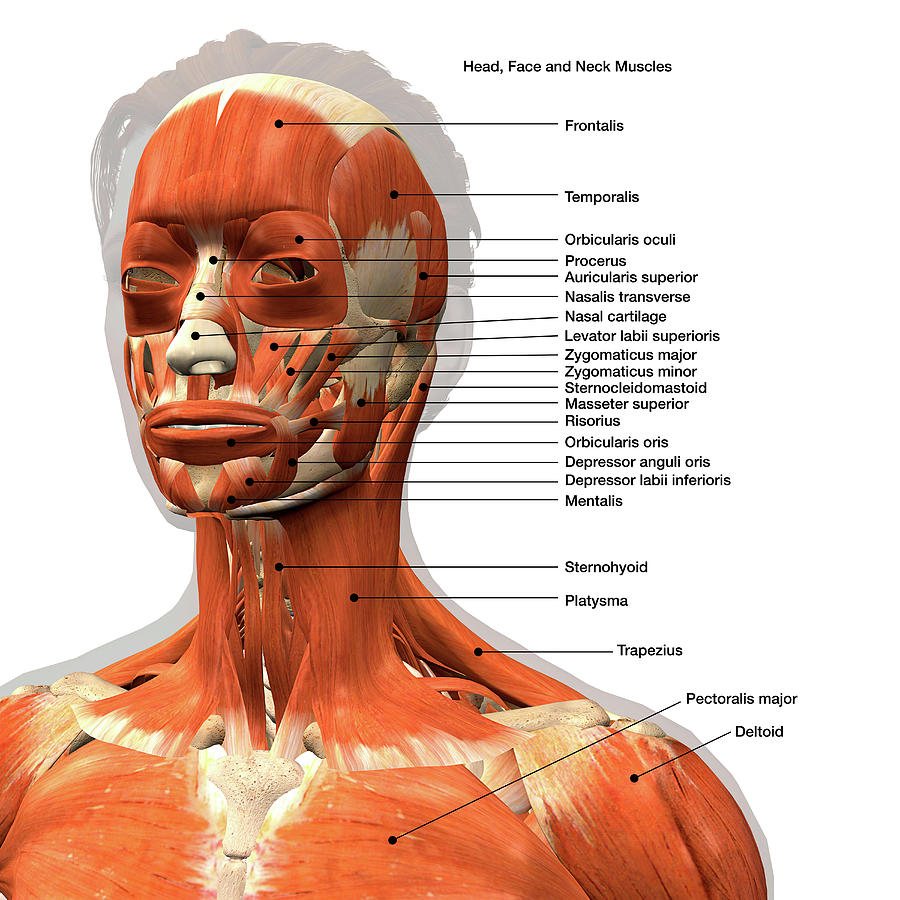

Labeled Chart Of The Facial Muscles Photograph by Hank Grebe Pixels

Neck Muscle Diagram Labeled Posted in diagrams scalenes muscles.

33 Label The Muscles Of The Head And Neck Labels Design Ideas 2020

Muscles of the neck / musculature of the cervical spine